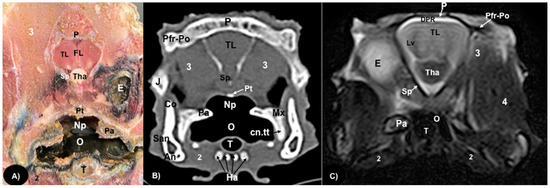

3.1. Anatomical Sections

3.2. Computed Tomography (CT)

3.3. Magnetic Resonance Imaging (MRI)